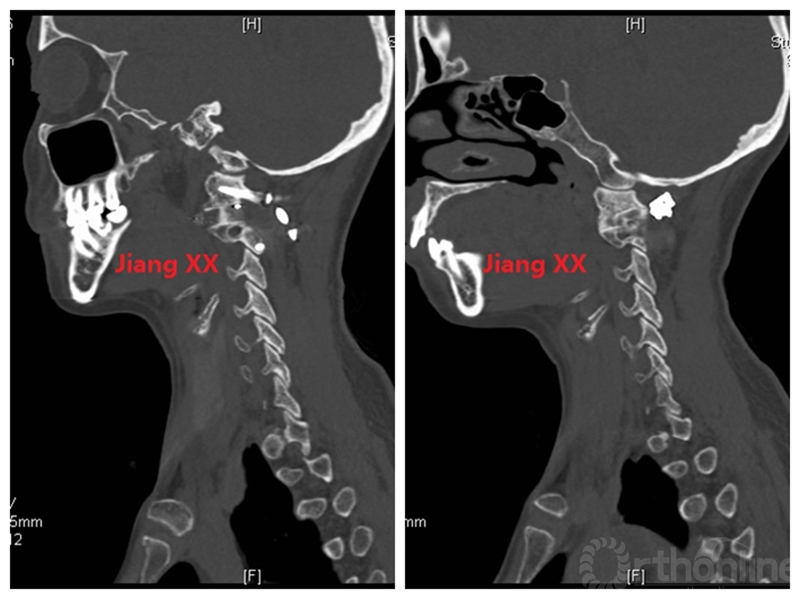

病例二:患者女性,58岁,主因“颈部疼痛伴转头受限半年”入院,诊断为寰枢椎半脱位。

术前CT

术后一年CT